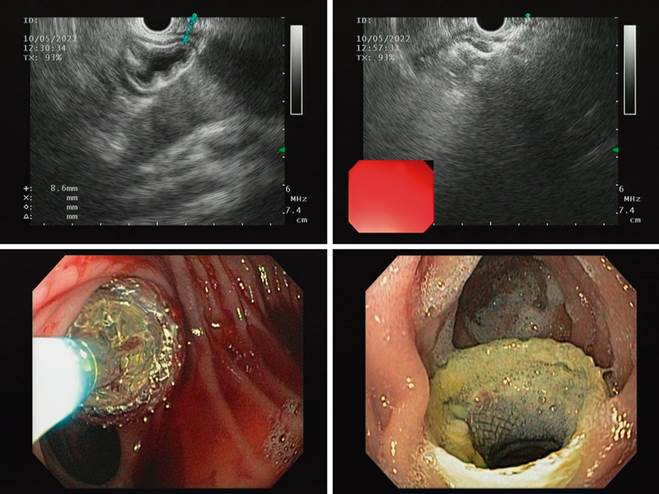

At the time, the patient had no symptoms, so we decided to perform the procedure in two stages: in the first stage, an EUS-guided jejunogastrostomy with apposing stenting, which allowed the complete expansion of the stent and maturation of the tract. In the second stage, one week after stenting, consisting of the usual ERCP, the side-viewing duodenoscope was advanced.

The first stage was performed under sedation, with EUS and fluoroscopic guidance. The remnant stomach was traced near the distal jejunum 10 mm from the gastrojejunal anastomosis. EUS-guided puncture with a 19G needle, instillation of water-soluble contrast medium in distilled water, and a gastrogram were performed. A 0.035-inch hydrophilic guidewire was advanced through the puncture needle, deploying the 15-mm apposing stent with a hot-tip introducer (Hot Axios 15 mm, Boston) in four steps. The deployment of the proximal tab in the afferent loop required further advancement of the pusher for release, given the limited space in this segment, which prevents the tip from getting away from the intestinal wall. The location of the stent was verified endoscopically with a slim front-viewing gastroscope (Figure 4).

In-hospital follow-up was carried out for 24 hours, with the absence of symptoms and adequate tolerance to the oral route, so the patient was discharged with an outpatient appointment for ERCP.